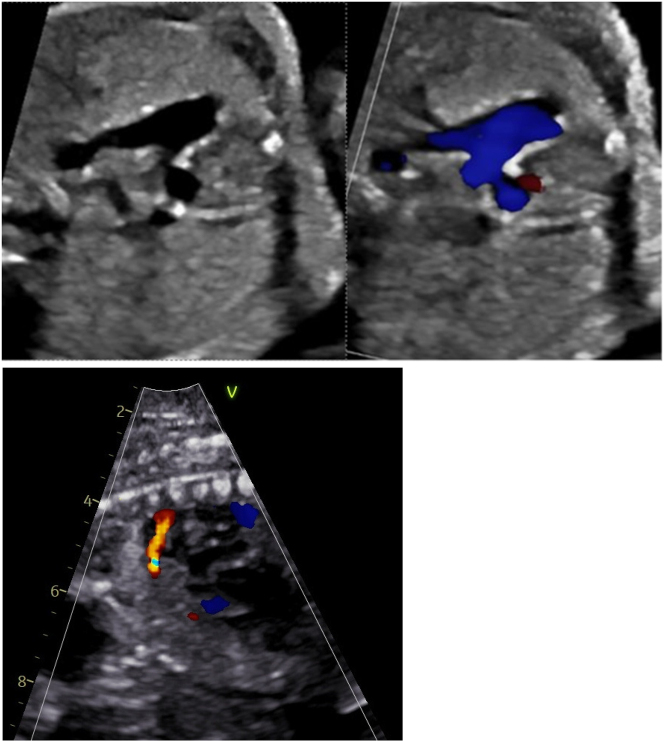

Case presentation: We describe a monochorionic diamniotic pregnancy complicated by twin anemia polycythemia sequence wherein the recipient twin developed signs of right heart failure secondary to premature ductus arteriosus constriction, requiring iatrogenic preterm delivery to avoid intrauterine demise.

Abstract Image